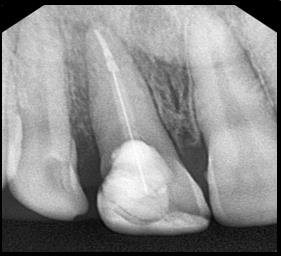

Question 11: Which materials cannot be seen in the print of the X ray?

Question 12: What option cannot be selected for the following X ray?

Question 13: What option cannot be selected for the following X ray?

Question 14: Which surface shows overhang restoration?

Question 15: Which surface shows overhang in the restoration?

Question 16: Which surface shows overhang?

Question 17: Which surface shows overhang?

Question 18: Which surface shows overhang?

Question 19: Which option can be chosen for the tooth # 3.6?

Question 20: which tooth shows defective resotration?